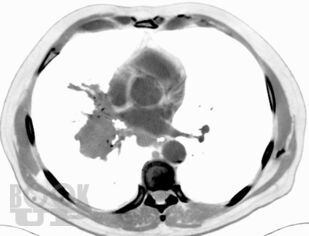

Представлено современное состояние проблемы различных форм злокачественных опухолей бронхолегочной системы, включая и паранеопластические проявления рака легкого. Представлены этиопатогенетические аспекты развития раковой болезни. Даны современные классификации рака легкого. Клиническая картина изложена систематизированно, с алгоритмом дифференциально-диагностического аспекта. Отражены последние достижения и перспективные исследования в диагностике рака легкого. Особое внимание уделено современным методам лечения рака легкого, показаниям и противопоказаниям к применению тех или иных методов лечения, особенно хирургического. Материал сопровождается подробными иллюстрациями.